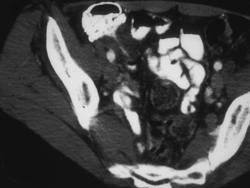

问题 男,42岁,右下腹痛、腹胀半年,无浅表淋巴结肿大,影像检查如图,最可能的诊断是 ( )

选项 A、肠结核 B、腹膜后纤维化 C、结肠癌 D、crohn病 E、淋巴瘤

答案 D